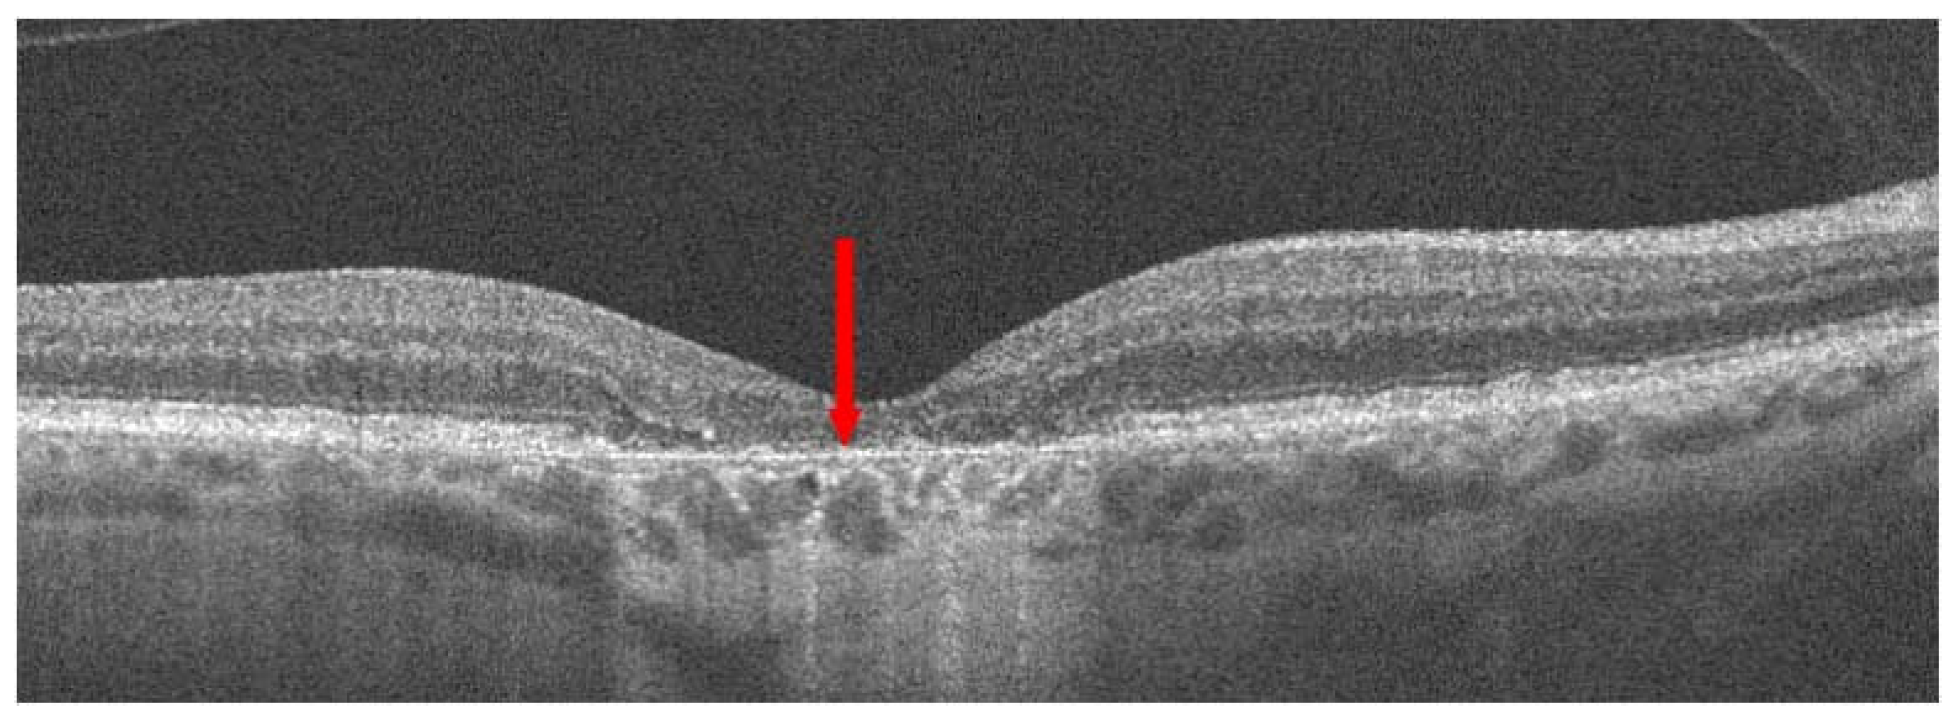

3. Treatment of Neovascular AMD

3.1. Photodynamic Therapy

3.2. Anti-VEGF Drugs

3.2.1. General Information